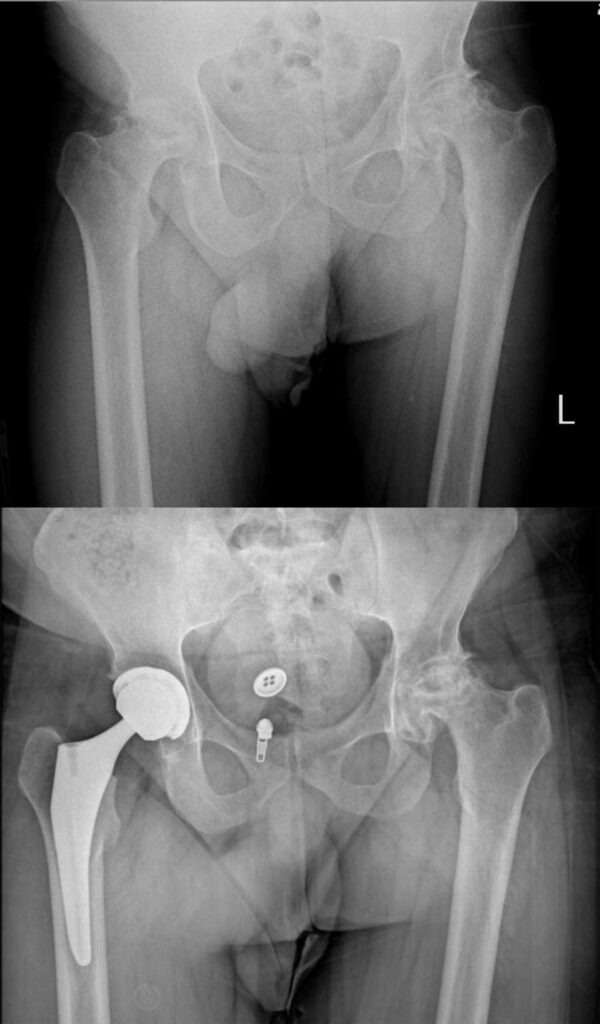

عکس تعویض مفصل لگن

برای آشنایی با تصاویر واقعی رادیوگرافی لگن قبل و بعد از جراحی، عکس تعویض مفصل لگن چند بیمار در زیر وجود دارد. با کلیک بر روی هر کدام از آنها تصویر بزرگتر و کامل را خواهید دید.